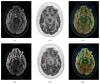

Case presentation: A 20-year-old patient was admitted for the evaluation of growth delay and hyperphagia. HbA1c level and fasting blood glucose were in the normal range. The diagnosis of hypothalamopituitary histiocytosis was based on histological features after biopsy of a large suprachiasmatic lesion identified on magnetic resonance imaging (MRI). Association of vinblastine and purinethol was started followed by a second-line therapy by cladribine. During the follow-up, the patient was admitted for recurrence of hyperglycemic states and extreme insulin resistance. The screening for serum anti-insulin receptor antibodies was positive. Each episode of hyperglycemia appeared to be correlated with tumoral activity and increase in serum anti-insulin receptor antibodies and appeared to be improved when the disease was controlled by chemotherapy.